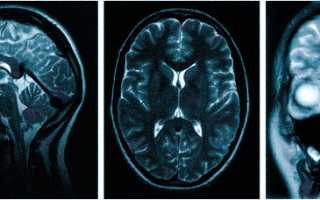

МРТ при головных болях (в трех проекциях): специальная программа выстраивает объемные изображения полученных срезов, что позволяет увидеть даже мельчайшие изменения и отдифференцировать патологию от нормы

Причин головной боли множество, и их не всегда возможно определить без помощи современных способов визуализации. Цефалгию вызывают: повышенное внутричерепное давление, сосудистые мальформации, опухолевые процессы, постравматические осложнения. Какую МРТ делать при головной боли или предпочтительней пройти КТ — зависит от предполагаемого характера патологии. Все методы являются взаимодополняющими, но что лучше в конкретном случае, выбирает врач с учетом жалоб, показаний и противопоказаний. МРТ и КТ с контрастным усилением позволяют получить сопоставимые по качеству снимки, но при этом используют разные принципы построения изображений. Чем раньше будет найдена причина и проведено адекватное лечение, тем больше шансов на полное выздоровление.